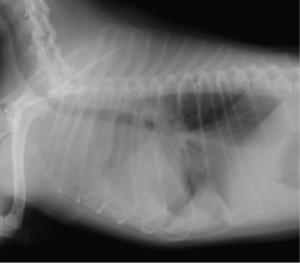

2回目の手術写真

再発時のレントゲンです。クリップが外れているなどの所見はありませんでした

右第10肋間より開胸しました。緑色を呈している部位が前回のクリップの位置です。尾側が2回目での結紮部位です

腹部正中切開から左腎臓を被膜切開により腹側に反転させました。大動脈直上の乳びが淡い緑のラインとして確認され、その先に乳び槽の塊が確認されます。これを破砕して切除しました